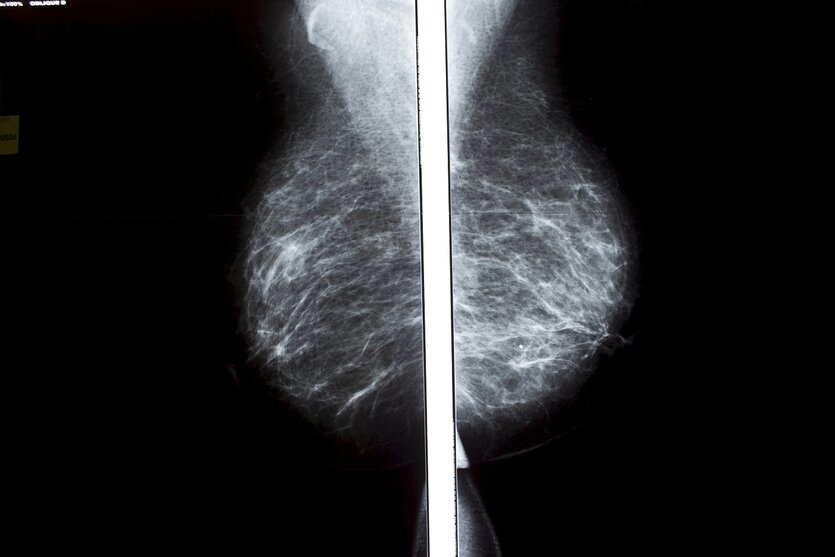

Mammographie einer weiblichen Brust: Wer den Befund nicht kennt, kann sich nicht behandeln lassen Foto: Marta Nascimento/REA/laif

Mehr als 2.000 Frauen wurden nach einer Brustkrebsvorsorgeuntersuchung nicht über das Ergebnis informiert, und das, obwohl die Mammographie „nicht eindeutig“ war oder „nicht klare Veränderungen“ zeigte. Jetzt wurde bekannt, dass es das Gesundheitssystem im südspanischen Andalusien monate-, ja in manchen Fällen jahrelang versäumte, die betroffenen Frauen zu benachrichtigen. Dabei hatte es erste Beschwerden über das Ausbleiben der Ergebnisse bereits 2023 gegeben.

Aus dem regionalen Gesundheitsministerium hieß es nun zuerst, die Frauen seien nicht benachrichtigt worden, um sie nicht „unnötig zu beunruhigen“. Die Fälle seien „grundsätzlich nicht schwerwiegend, sollten aber außerhalb der Vorsorge unter medizinischen Kriterien überwacht werden“, ergänzte eine Pressemitteilung der andalusischen Regierung. Nur: Wer den Befund nicht kennt, kann sich schlecht überwachen lassen.